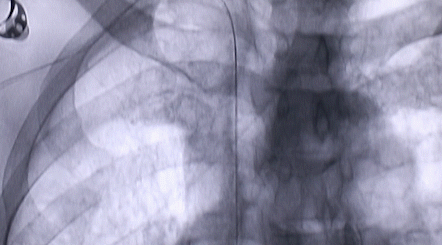

1月12日,西安國際醫(yī)學(xué)中心醫(yī)院心臟外科郭穎強主任團隊成功為一名腹主動脈閉塞、右側(cè)腎動脈閉塞、左側(cè)腎動脈重度狹窄、腹壁淺表動脈側(cè)支循環(huán)形成、高血壓病3級(極高危組)合并閉塞性周圍動脈粥樣硬化、急性腎功能不全的老年患者實施腎動脈球囊擴張 腎動脈支架植入術(shù) 動脈血栓抽吸術(shù) 髂動脈開通術(shù),治好了困擾患者多年的頑固性高血壓。患者目前康復(fù)良好,將于近日出院。

按照術(shù)前制定的方案,郭穎強主任和楊金保博士首先嘗試開通閉塞的右腎動脈,但由于血栓機化、鈣化嚴重,右腎動脈難以開通。遂謹慎擴張狹窄的左腎動脈,并成功植入一枚支架。之后經(jīng)過反復(fù)旋磨、抽吸,順利開通髂動脈,但腹主動脈閉塞段仍難以擴通。此時,患者居高不下的血壓很快恢復(fù)到正常水平。